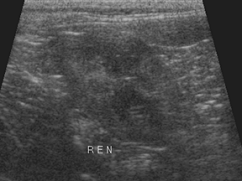

Рис.3. Полікистоз правої кирки кота

4 років, фрагменти сканограм

Розміри кист можуть коливатися від 1

мм до 1 см і більше. З віком їх розмір і кількість збільщуються аж до повного

заміщення нормальної структури нирки різнокаліберними порожнинами. Досить часто

аналогічні кисти можливо виявити в ураженої полікистозом тварини і в інших

органах - підшлунковій залозі, печінці, матці. По мірі прогресування

захворювання і порушення нормальної структури нирок не може не знизитися їх

функція. Зниження функції нирок характеризується хронічною нирковою

недостатністю, що, як правило, є першим тривожним симптомом цього захворювання.